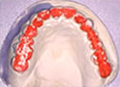

ブラキシチェッカー

就寝時に1日か2日装着し、どこで一番歯ぎしりしているかチェックします。

これにより一番歯に負担のかかっているところがわかります。